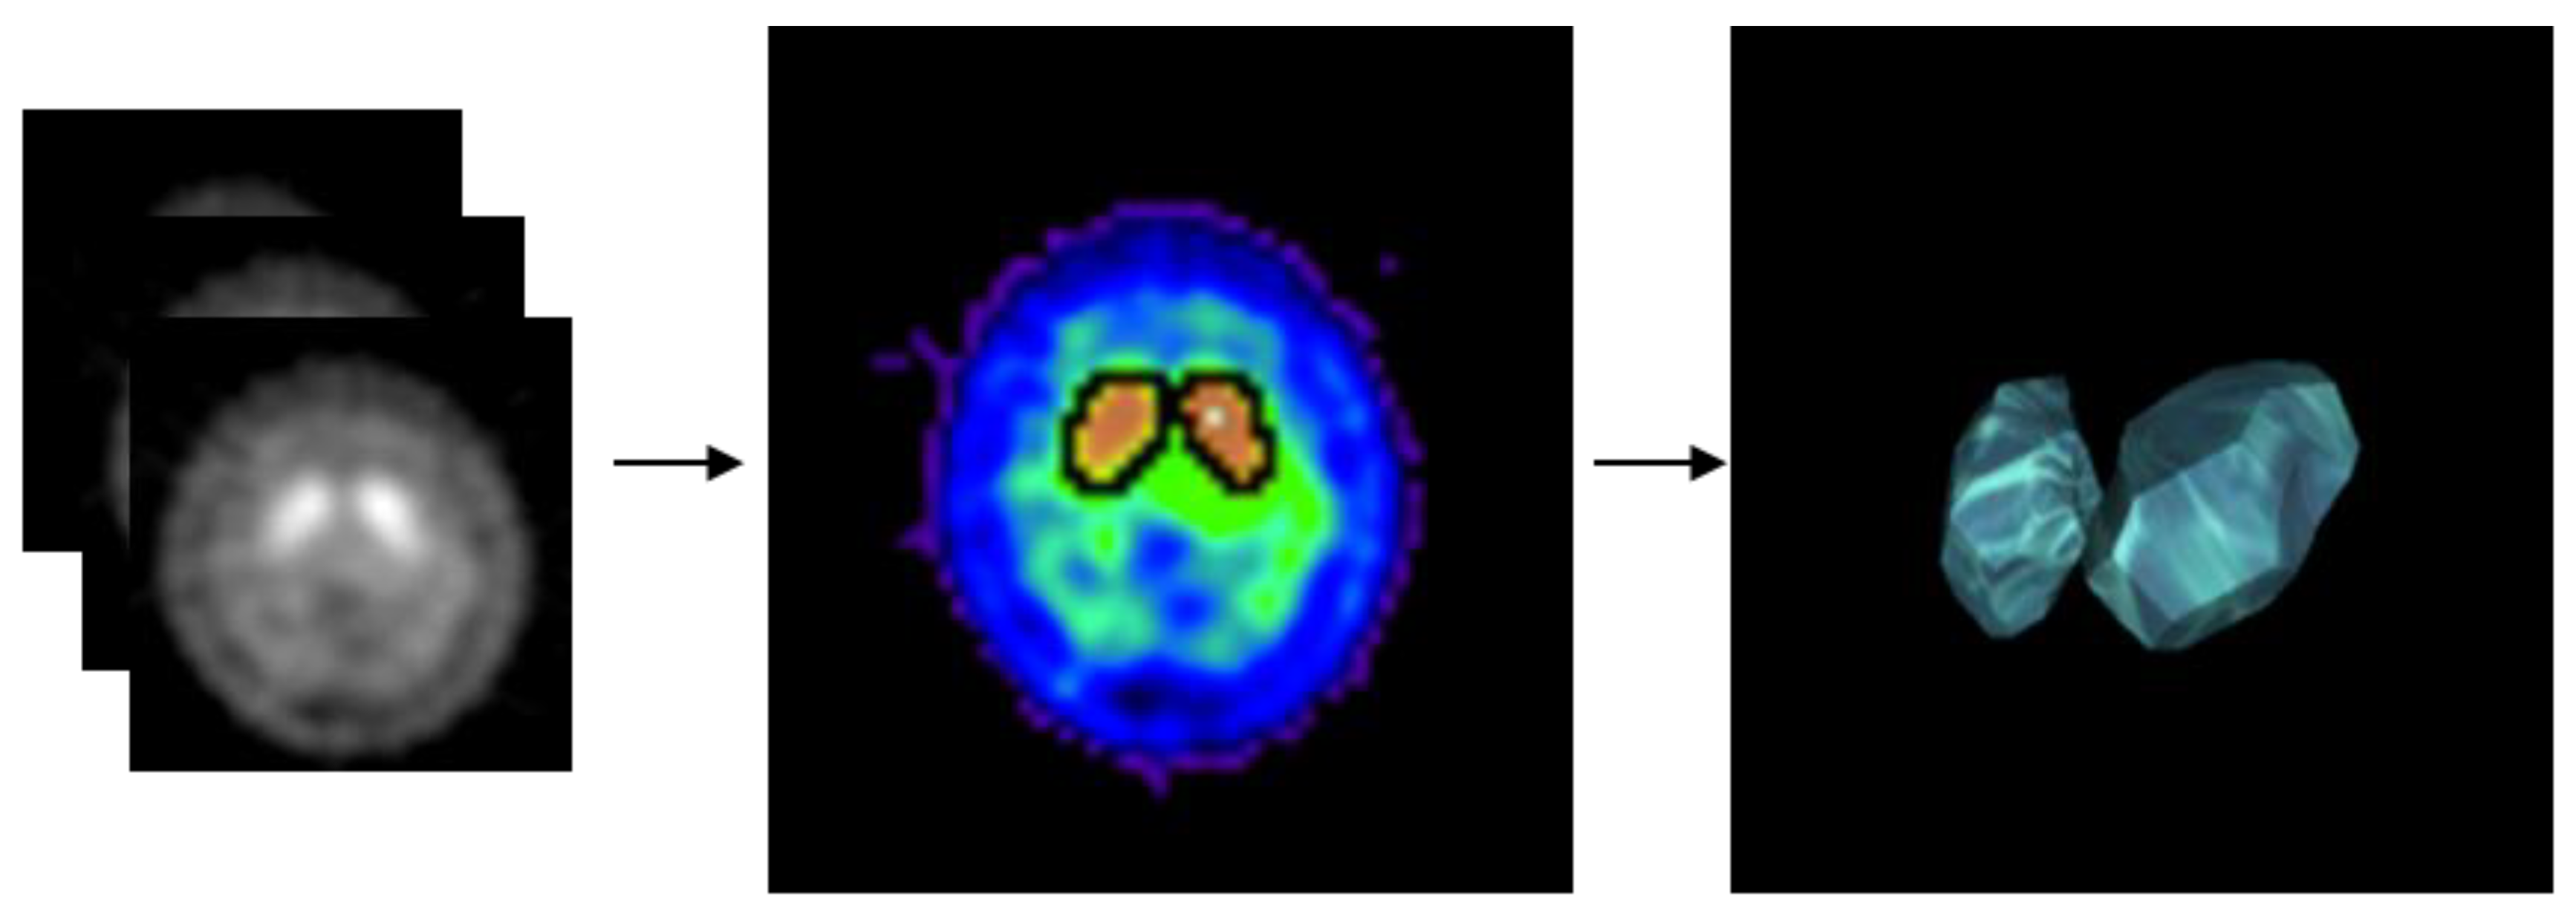

2.3. Experimental Design